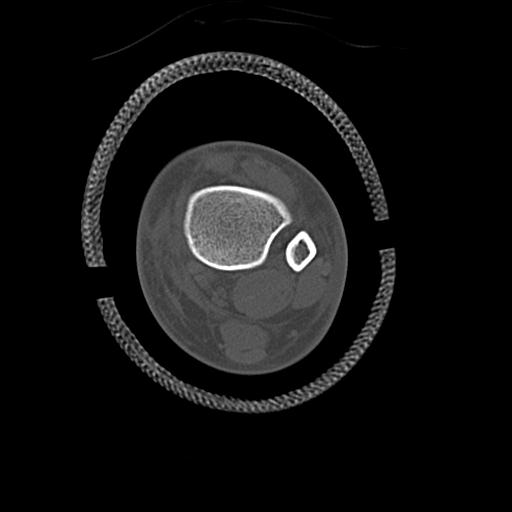

56476 8/28 4R 1/21 2R 左足関節 デジカメ写真 72歳女性 右足関節AS